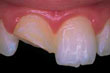

ChippedDinte frontal fracturat

Dinte parţial fracturat: Dacă nu există durere şi fragmentul desprins este mic, puteţi decide singur dacă, cum şi când doriţi repararea lui. În funcţie de dimensiunea fragmentului desprins, dintele poate fi şlefuit sau corectat prin proceduri de cosmetică dentară. Alte opţiuni includ faţetarea, reconstituirea coronară şi obturaţia. Rugaţi medicul dentist să vă prezinte aceste soluţii. Dacă fractura s-a produs la suprafaţa unei obturaţii sau la un dinte artificial, se impune înlocuirea acestora.